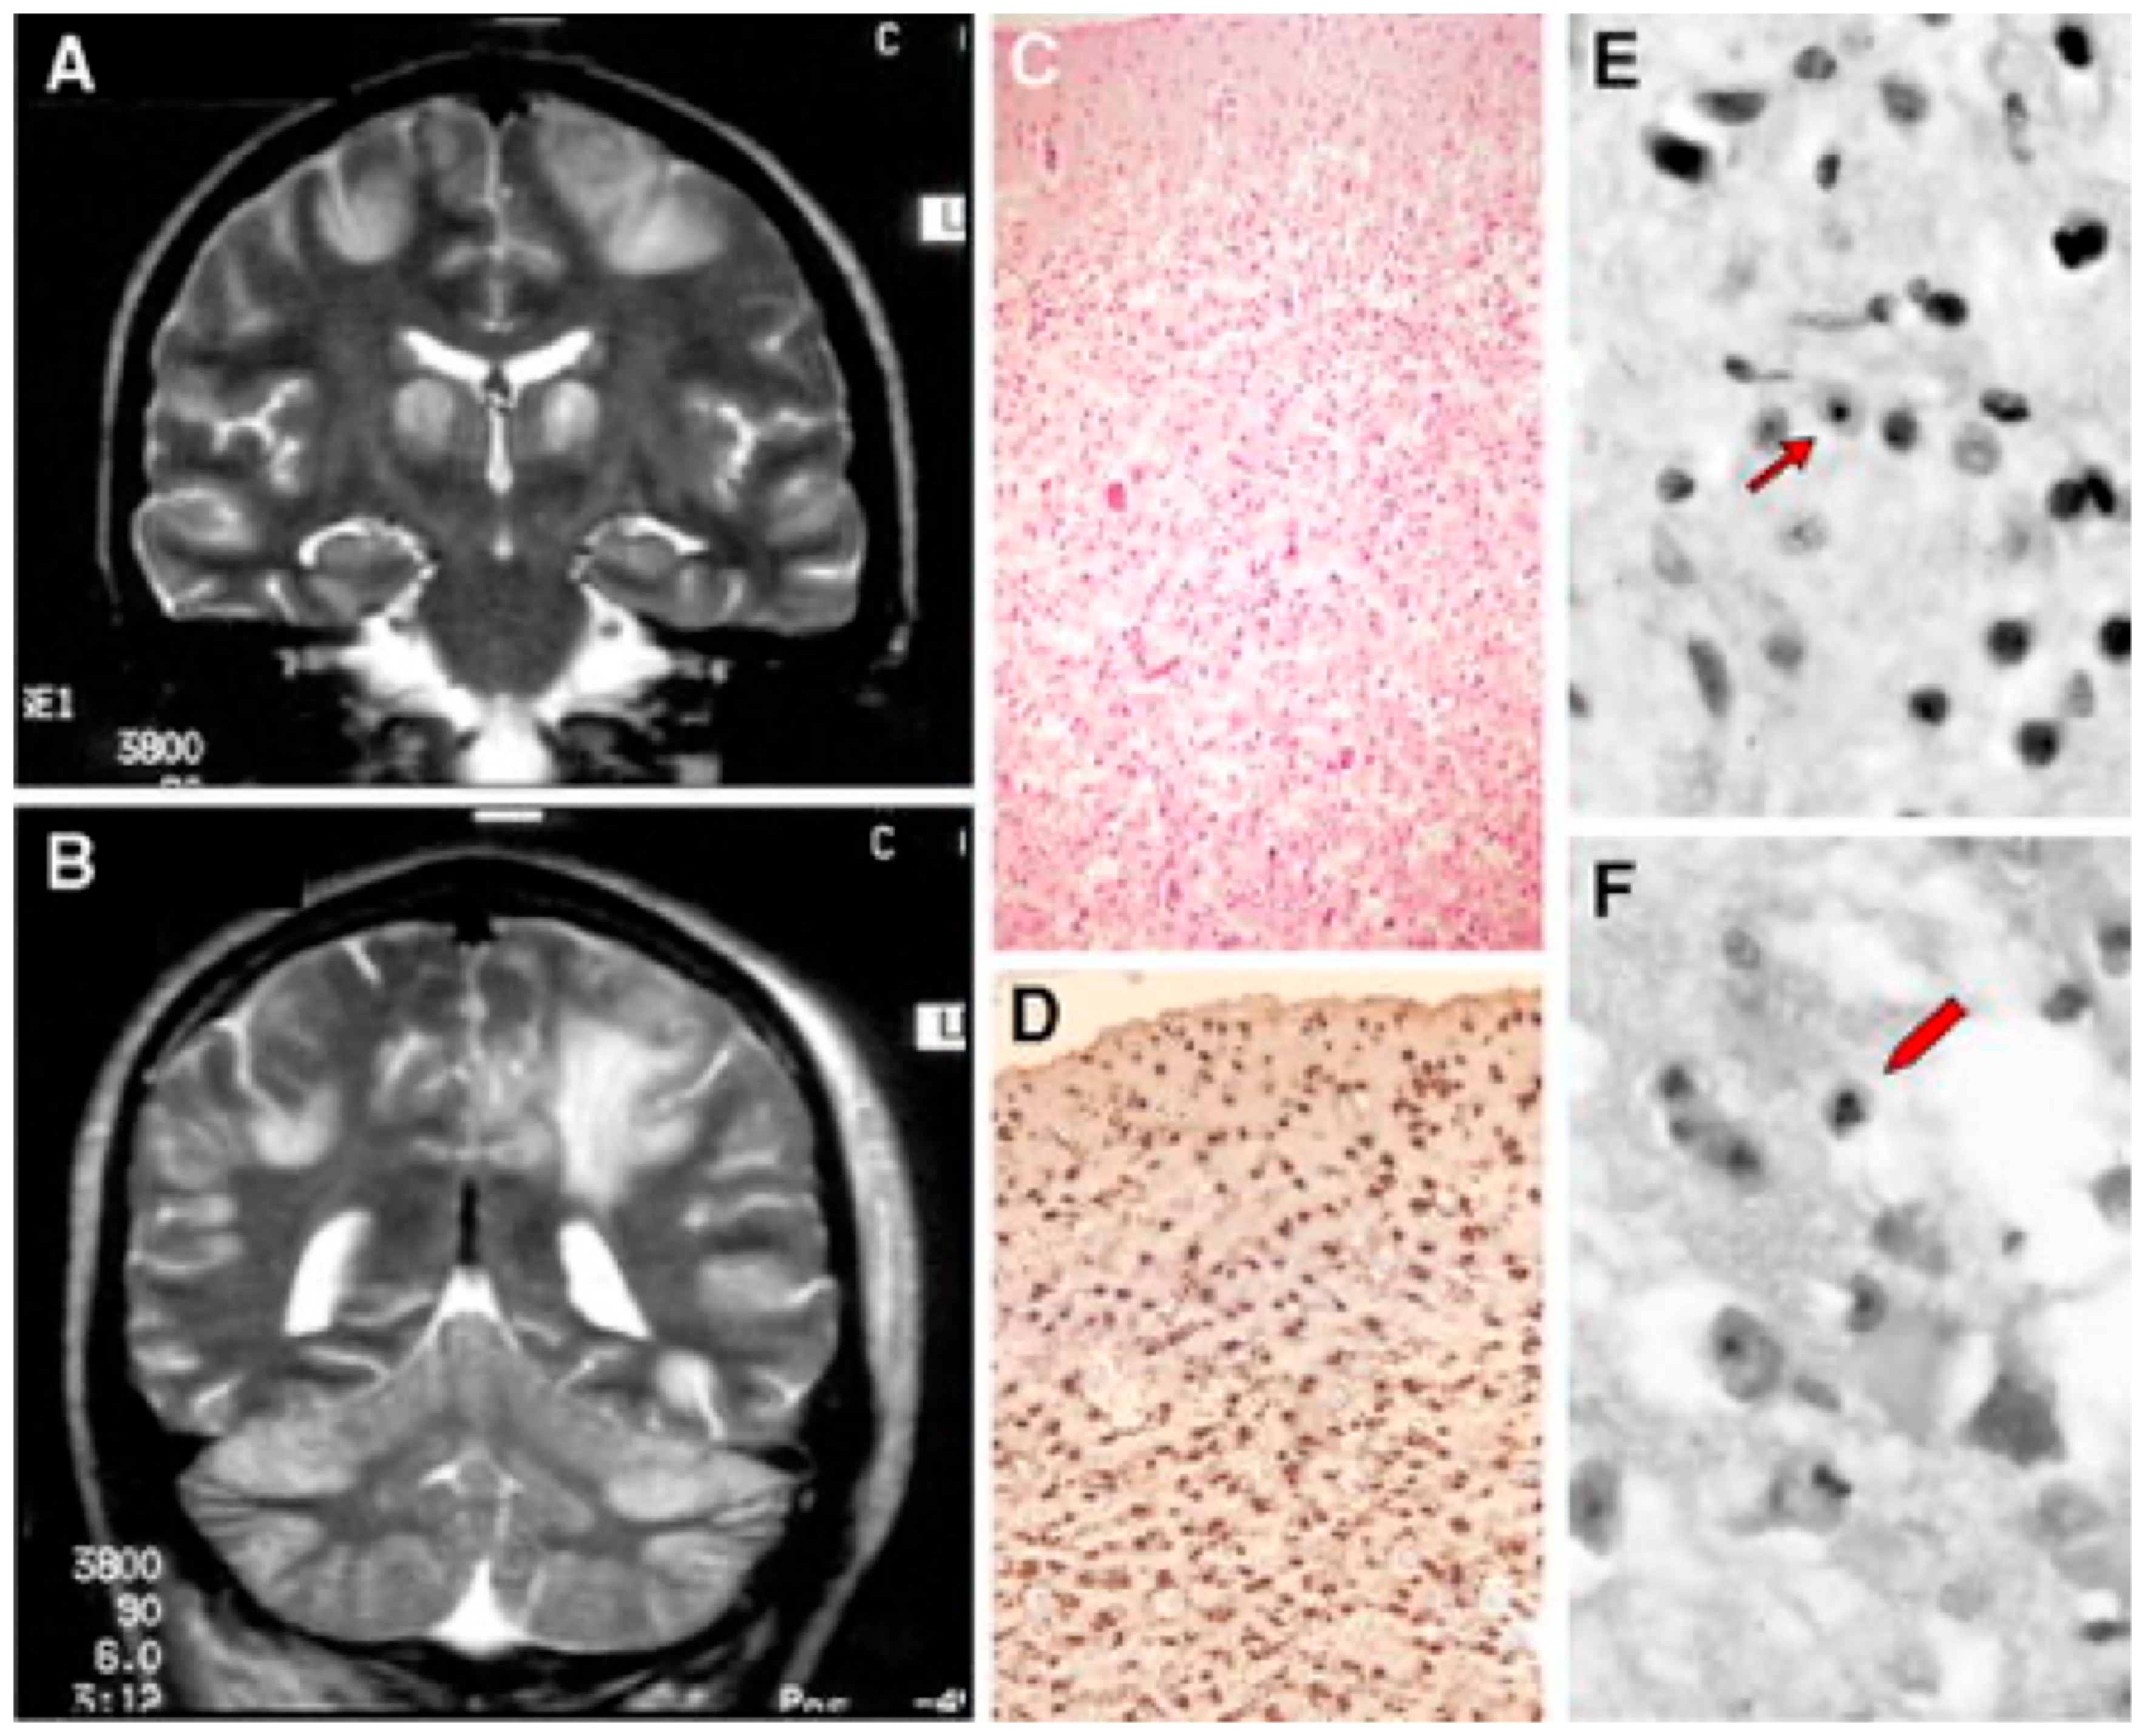

- Simonati, A.; Filosto, M.; Savio, C.; Tomelleri, G.; Tonin, P.; Dalla Bernardina, B.; Rizzuto, N. Features of Cell Death in Brain and Liver, the Target Tissues of Progressive Neuronal Degeneration of Childhood with Liver Disease (Alpers-Huttenlocher Disease). Acta Neuropathol. 2003, 106, 57–65. [Google Scholar] [CrossRef] [PubMed]